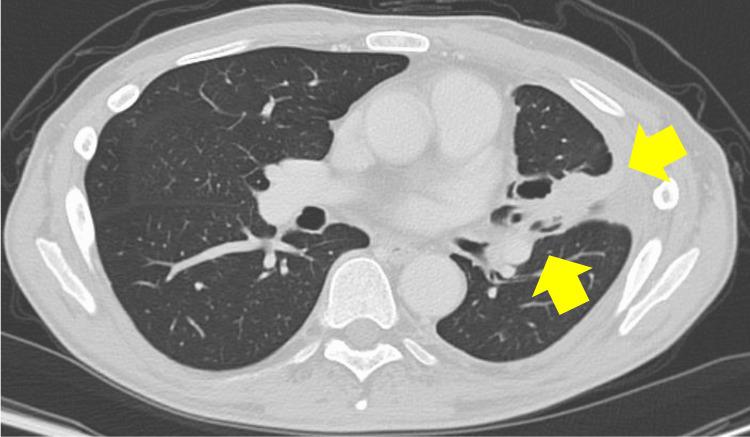

Paroxysmal nocturnal hemoglobinuria (PNH) is a rare hematologic disorder characterized by complement‑mediated intravascular hemolysis. Although breakthrough hemolysis (BTH) is typically triggered by infections or surgery, chemotherapy-induced BTH is seldom reported, and optimal management strategies during cytotoxic cancer therapy remain undefined. We report a 52‑year‑old man with longstanding PNH who developed stage IVA epidermal growth factor receptor‑mutated lung adenocarcinoma. After discontinuing first‑line osimertinib due to diarrhea, second‑line carboplatin-pemetrexed (chemotherapy regimen consisting of carboplatin and pemetrexed) induced severe BTH, evidenced by lactate dehydrogenase rising to 2,462 U/L and hemoglobin (Hb) dropping to 4.6 g/dL. Introduction of ravulizumab promptly normalized lactate dehydrogenase (<250 U/L), raised Hb to 10.5 g/dL, and suppressed total hemolytic complement activity (<14 U/mL). Although mild hemolysis recurred before subsequent cycles, administering ravulizumab before each chemotherapy session prevented further episodes. The patient completed 14 cycles without transfusion or thrombosis and achieved a progression-free survival (PFS) of two years and five months, far beyond the ~5.5 month median for this regimen. Personalized scheduling of ravulizumab enabled uninterrupted cytotoxic chemotherapy by effectively managing BTH, suggesting that sustained complement C5 inhibition may confer oncologic benefits. Prospective studies are warranted to evaluate the broader impact of complement blockade in patients with PNH and malignancy.

阵发性睡眠性血红蛋白尿(PNH)是一种罕见的血液系统疾病,其特征为补体介导的血管内溶血。尽管突破性溶血(BTH)通常由感染或手术引发,但化疗诱导的BTH鲜有报道,且细胞毒性癌症治疗期间的最佳管理策略仍不明确。我们报告了一名52岁患有长期PNH的男性,他罹患了IV期表皮生长因子受体突变的肺腺癌。在因腹泻停用一线奥希替尼后,二线卡铂-培美曲塞(由卡铂和培美曲塞组成的化疗方案)诱发了严重的BTH,乳酸脱氢酶升至2462 U/L以及血红蛋白(Hb)降至4.6 g/dL可证明这一点。使用ravulizumab后,乳酸脱氢酶迅速恢复正常(<250 U/L),Hb升至10.5 g/dL,并抑制了总溶血补体活性(<14 U/mL)。尽管在后续周期前再次出现轻度溶血,但在每次化疗疗程前给予ravulizumab可预防进一步发作。该患者完成了14个周期,未发生输血或血栓形成,并实现了两年零五个月的无进展生存期(PFS),远远超过了该方案约5.5个月的中位数。通过有效管理BTH,ravulizumab的个性化给药方案使细胞毒性化疗得以不间断进行,这表明持续抑制补体C5可能带来肿瘤学益处。有必要进行前瞻性研究,以评估补体阻断对PNH和恶性肿瘤患者的更广泛影响。